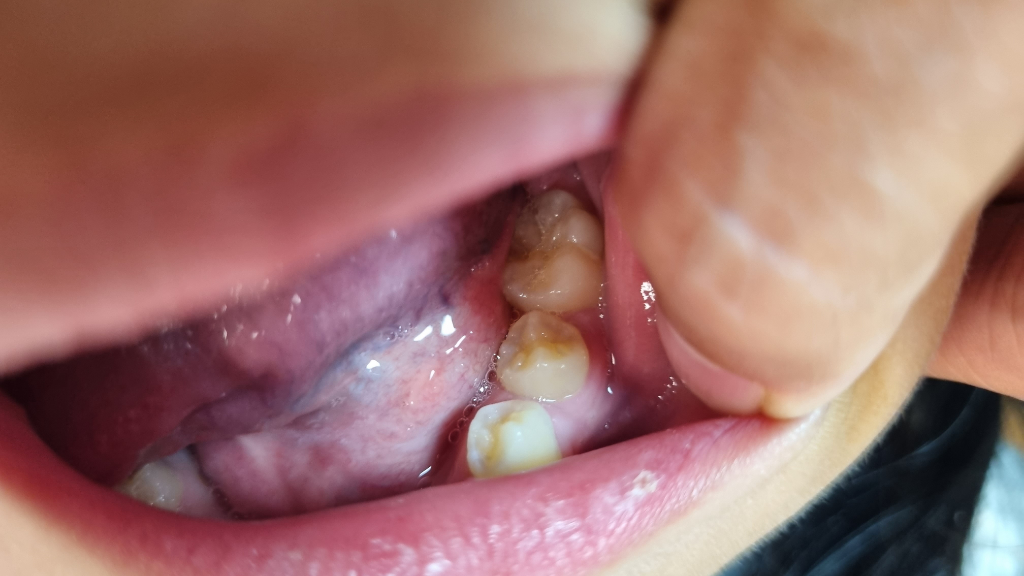

아이 맹출중인 영구치 어금니 모양 방향?

사진에 왼쪽(L)부분이 한 45도정도 모양이 틀어져서 났다고 하네요. 오른쪽(R)과 비교시 그러긴합니다. 선생님께선 특별히 저정도로 교정까진 안해도될것같다고 나중에 본인이 씹는데 불편하다던지 음식이 잘안씹히다던지 하는등의 불편감이 있다면 선택적으로교정해도될것같다고 들었습니다. 그런데 저 뾰족하게솟은부분이 씹을때 윗치아에 닿으면 윗치아에도 안좋은게아닌가하는 의문이 문득 들어서요. 그냥 둬도 괜찮은건가요?

(맨위 좌우비교사진상 어금니에 하얀건 뭐가묻은거에요,;;)

방사선 사진과 추가된 임상 사진을 보니 치외치는 아닌 것 같습니다

물론 치외치 여부와 상관없이 소구치의 회전맹출로 교두가 위,아래 맞물릴 때 정확히 교합 지점을 찾지 못하여 깨지거나 마모되기 쉬운 것은 맞습니다

이미 어느정도 맹출하고 자리를 잡은 상태라 더 이상 여기서 올바르게 배열되기는 힘들 것 같습니다